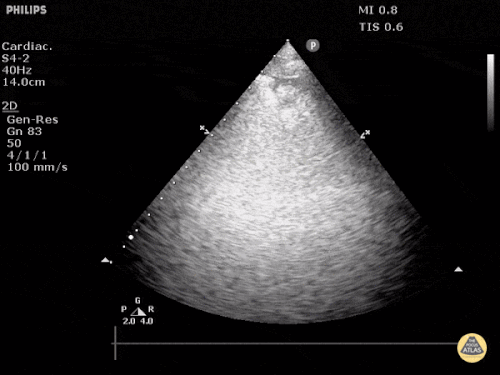

Question 3: You are called to evaluate a patient at a CATS call on M5. The patient is a 99-year-old man with diastolic dysfunction. His diuretics have been held for the past week due to renal dysfunction (currently his creatinine has plateaued at 4.8 mg/dL). He has been placed on BiPAP but continues having substantial work of breathing. The following images are obtained from his right thorax:

- Describe the ultrasonographic findings (Do you think this is a bird or a plane? Superman?)

- What is your diagnosis?

- What is the best therapeutic strategy for this patient?